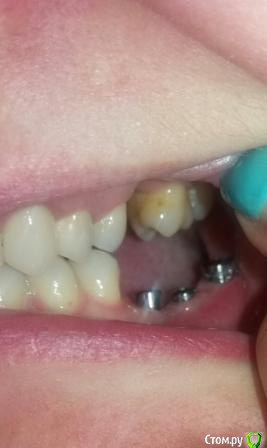

Oksana-p Опубликовано 23 мая, 2016 Автор Поделиться Опубликовано 23 мая, 2016 Ну 8й не проблема. Что касается остального, то нужны новые снимки и желательно внутриротовые фото Если подойдет -то вот фото на телефон (извиняюсь за качество, вечером попрошу кого-нибудь сфотографировать) Ссылка на комментарий

Oksana-p Опубликовано 24 мая, 2016 Автор Поделиться Опубликовано 24 мая, 2016 Еще сфоткала. На снимок ехать 200 км. Мне хирург почему-то его после установки формирователей даже не сделал. Как назло, и десна возле последнего импланта слева болит при надавливании и ноет. Полощу хлоргексидином. Позвонил хирург, сказал, что у меня все "в норме", что у меня уже лучше ничего не получится, что слишком тонкая кость, типа - скажите спасибо "хоть так поставили". Ссылка на комментарий

Oksana-p Опубликовано 15 июня, 2016 Автор Поделиться Опубликовано 15 июня, 2016 Вот такая ситуация сейчас..... Ссылка на комментарий